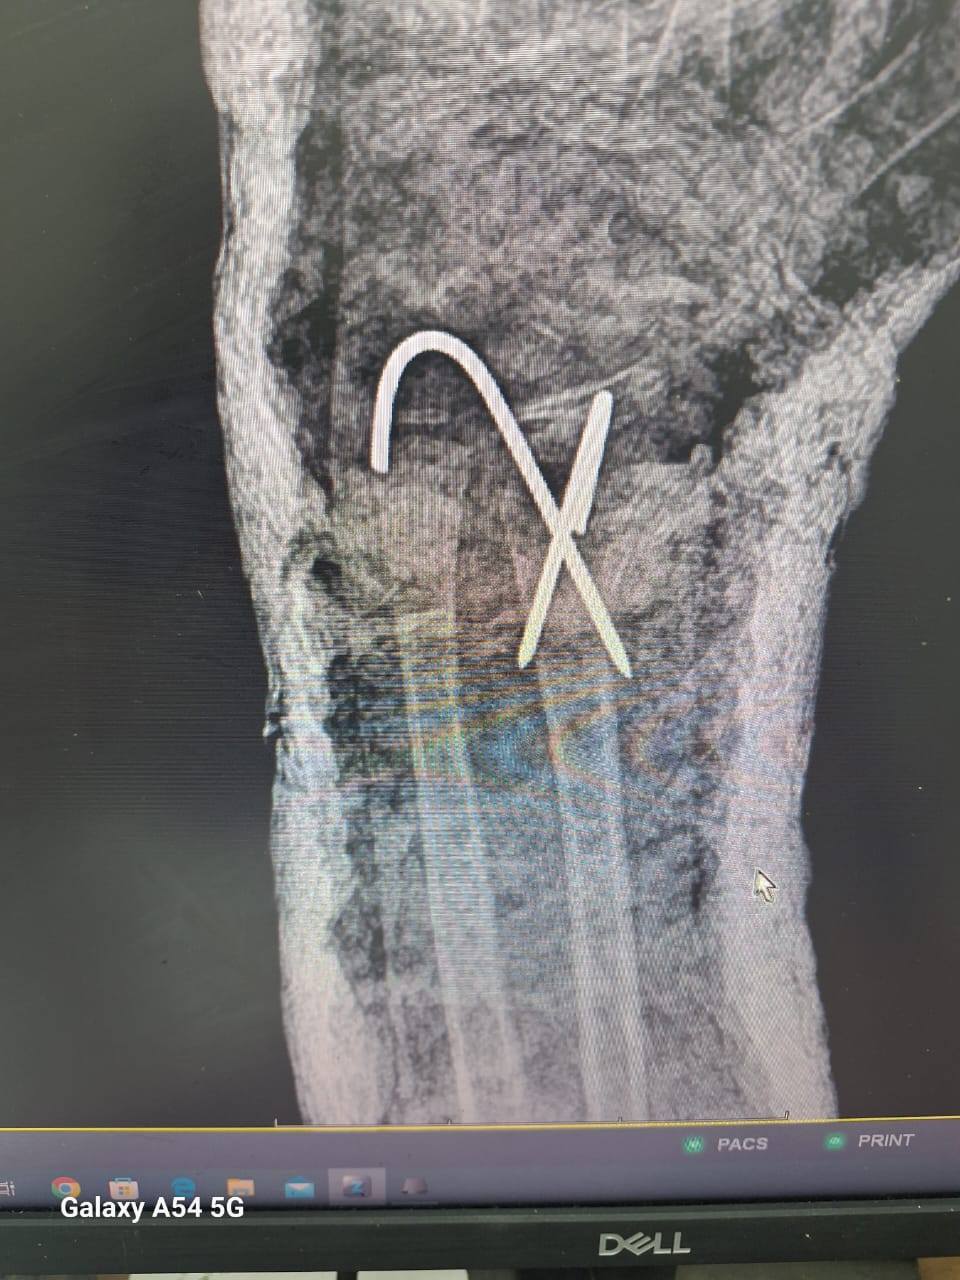

مضيفاً ، إلي أنه تم إجراء 3 عمليات بقسم الأنف والأذن، و3 عمليات بقسم العظام، بالإضافة إلى 4 عمليات جراحية متنوعة، بما يعكس جاهزية الأقسام المختلفة بالمستشفى لتقديم خدمات طبية متكاملة للمرضى